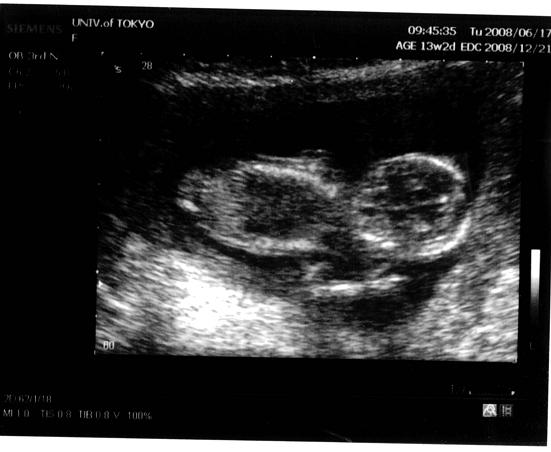

今日は初めての経腹エコー。

お腹の上からはまだあんまり見えないかなーって言われて見たけど、しっかり見えました♪

ヒョコヒョコ動いてた!

先生「ピースしてるよ!」だって。ホント!ピースに見えるかも!!

その後は、経膣エコーで。間10分ぐらいあったんだけど、

「あれ?寝ちゃった。でも首の後ろ見ようね」だそうで、しっかり首のむくみを見てくれました。

結果は「計るのが難しいくらい腫れてないよ。良かったね」これって、羊水検査をする予定のないワタシには、かなりホッとする一言。

で、「ちょっと起こしちゃおうか~」とツンツンしたら

「おっ、起きた!お手手で顔ゴシゴシ擦ってるよ。判る?」

はい!判ります!!ゴシゴシやってる~♪

先生「あっ!怒っちゃった!すごい元気な子だね~」

思いっきり脚まげて、ワタシのお腹を元気いっぱい蹴ってます。バシバシ何度も!

可愛すぎ~~~!!!

先生いわく、「もうちょっと経ってコレくらい元気に蹴ったら、可愛いじゃなくってイテテになるよ~」だって。楽しみ!!

ちなみに、最初エコー入れてすぐに、先生が「あっ!」

・・・股間側の下から写ってました。このアングルはっ?!って感じだったんだけど、あっという間にアングル変えられちゃいました。

今日の先生は、「22wまで絶対性別教えない」んだそうで、聞けなかったけど。

どっちか判っちゃったのかな?とか、思ったり。。

だって、この週数だと経膣で股間が写ればどっちか判るって言ってたし。

最初は男の子希望のワタシ&絶対女の子だと思い込んでるムコちゃん

さ~てどっちかなぁ~♪